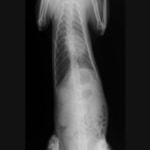

レントゲン画像

・ 胸部レントゲン検査:胸水貯留

■ 症例1 2歳、柴犬、去勢雄

主訴:発咳の頻度増加、努力性呼吸